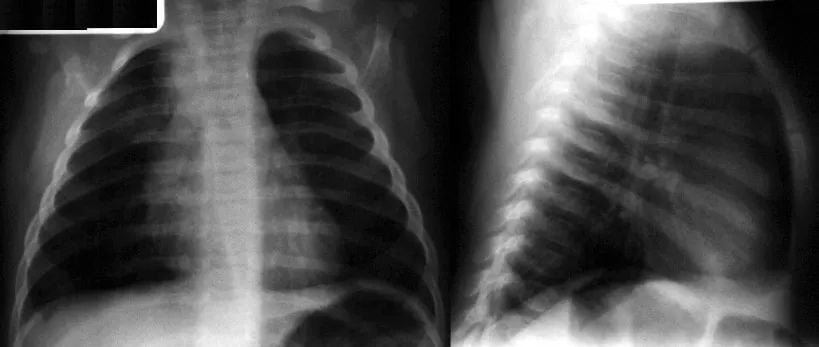

A 3-year-old boy presents with a 1-week history of worsening congestion and cough with persistent fever. His lung examination reveals rales, and a chest radiograph is shown in the figure below.

The stem features a preschooler and a CXR, tempting you toward “bacterial CAP = atypical coverage,” but the question asks for a global truth about diagnosis and treatment—most reliable statement is the macrolide recommendation for school-aged atypical CAP.